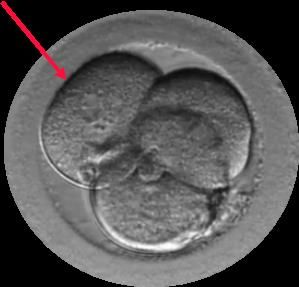

El Dr. Borja Marquès es el autor del estudio “Signos de auto-reparación de los embriones en el laboratorio de FIV” cuyas conclusiones apuntan que los embriones poseen un mecanismo de auto-corrección ignorado hasta hoy. Según este trabajo que se presenta esta semana en Murcia, en el 36º Congreso de la Sociedad Española de Ginecología (SEGO), embriones que han sufrido división reversa (desaparición de alguna de sus células) o multinucleación (presencia de dos o más núcleos en alguna de sus células) pueden acabar con éxito, es decir, con un embarazo normal y el nacimiento de un bebé sano.

Gracias a los incubadores con cámaras time-lapse (Embryoscope), en los laboratorios de Institut Marquès ha sido posible captar las imágenes de embriones con división reversa reabsorbiendo sus propias células y de embriones multinucleados expulsando las células anómalas en el 4º o 5º día de vida. Para conseguirlo, se ha analizado el desarrollo de 21.274 embriones, desde su fecundación hasta que llegaron a blastocisto.

“Nos estamos cuestionando todo los fenómenos de división embrionaria que, hasta hoy, se consideraban un mal pronóstico. De momento, ya hemos demostrado que en el caso de la división reversa y de los embriones con multinucleación, no hay evidencia científica que aconseje descartarlos de entrada. Hay que ver cómo evolucionan hasta su quinto día de vida y comprobar si han conseguido auto-repararse antes de decidir si son aptos para implantarse en el útero materno y capaces de dar lugar a un niño sano.” declara el Dr. Borja Marquès, ginecólogo especialista en Reproducción Asistida. “Nuestro trabajo da elevadas oportunidades de vida a embriones que hasta hoy hubieran sido desechados. De esta forma, estamos ofreciendo nuevas opciones a nuestros pacientes” añade el Dr. Marquès.